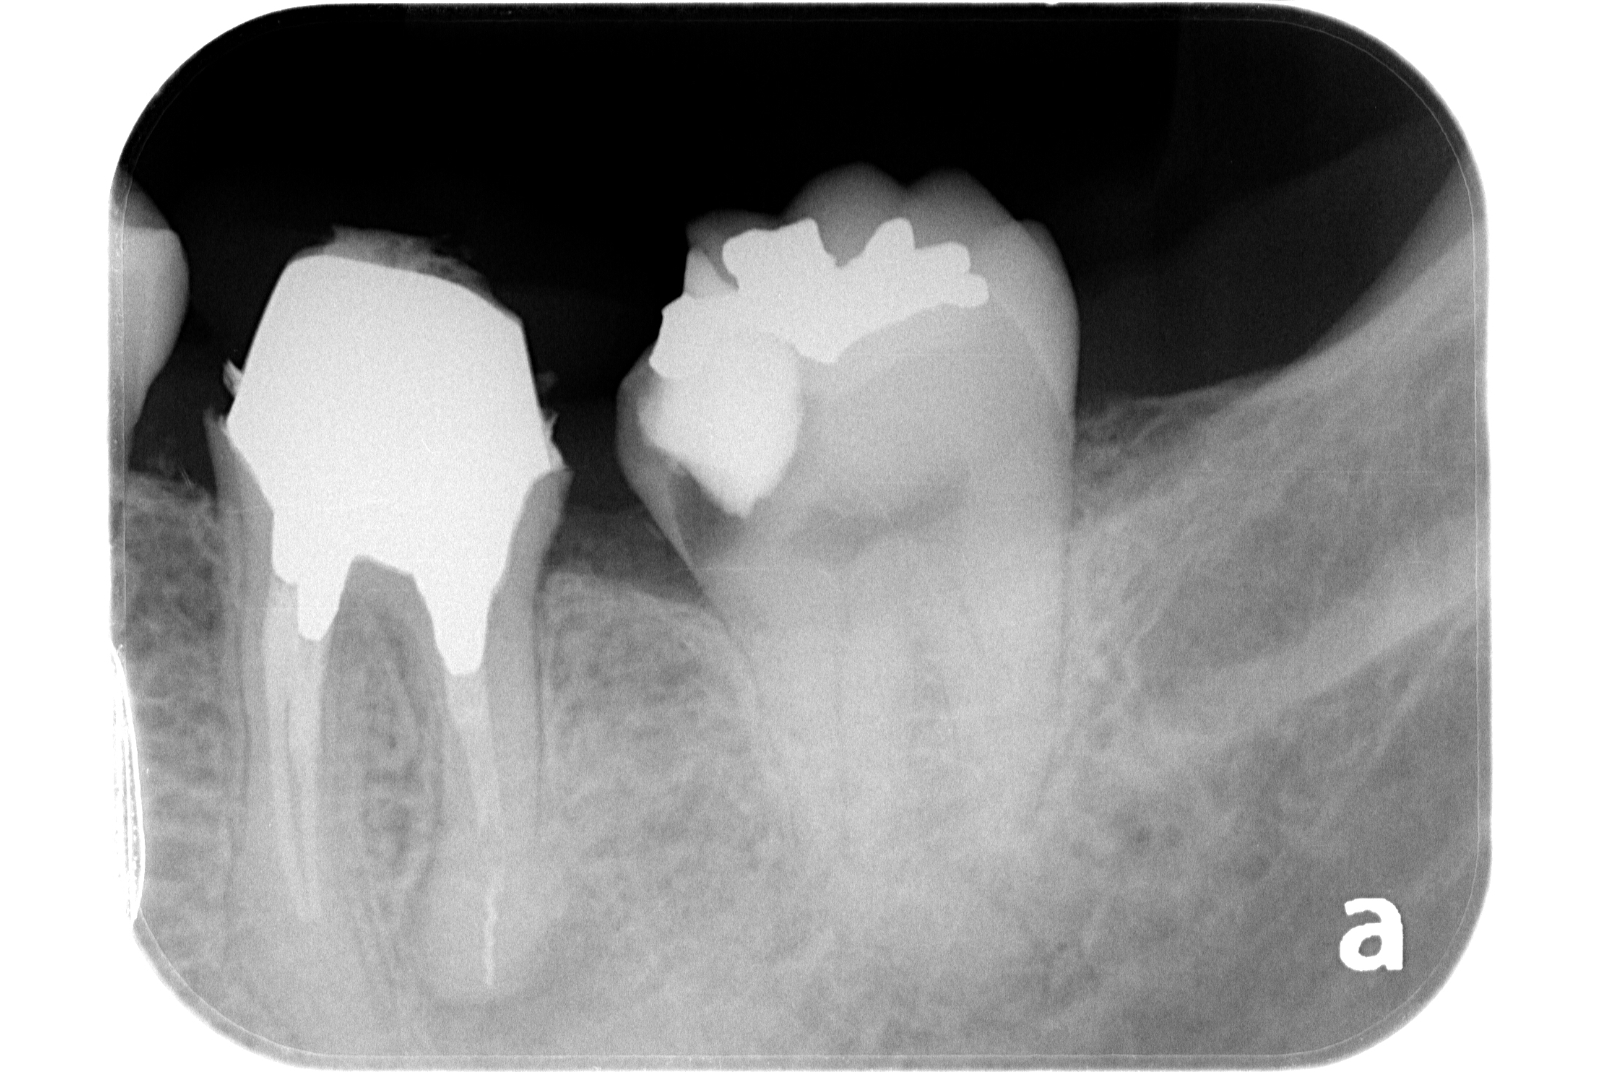

治療例 写真とレントゲン

治療前

治療後

※治療例に記載の情報はあくまでも症例に対してのものとなります。

| 費用 | 隔壁 11,000円(税込) |

|---|---|

| 初回根管治療 大臼歯 143,000円(税込) | |

| 支台築造 レジンコア 11,000円(税込) | |

| 治療期間 | 1週間 |

| 治療回数 | 2回 |

| 主な副作用とリスク | 根管治療が奏功しなかった場合、外科的歯内療法へ移行します。 |